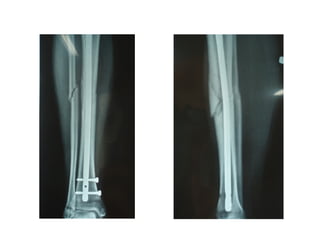

• #5 3 razões: lembrar que a radiografia se dá em um único plano e, portanto, mais de um plano é importante para se ter certeza que a lesão existe ou não (já que esta pode aparecer em uma incidência, mas não na outra) e para determinar o alinhamento das fraturas. Aqui está o link para se falar de posicionamento

• #6 A mesma fratura. Uma vista em ap e outra em perfil. Isso mostra que a mesma imagem toma formas diferentes dependendo da incidência. Por isso é importante ter duas incidências no mínimo, pois elas se complementam